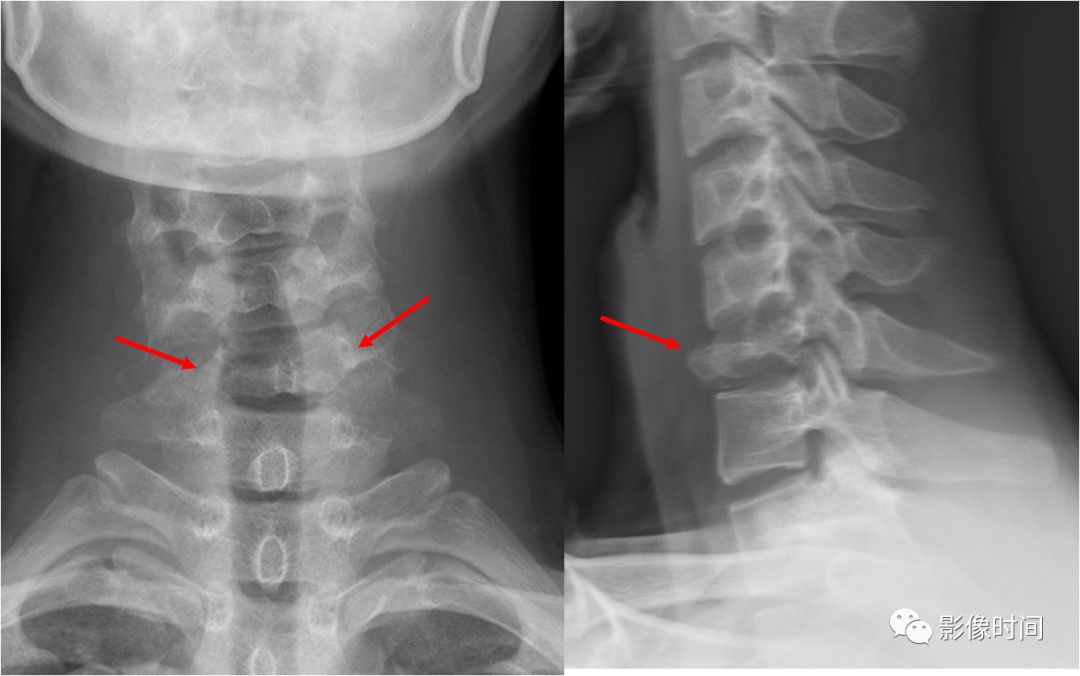

6

肥胖第 2 颈椎征

肥胖第 2 颈椎征(the fat C2 sign)

所谓肥胖第 2 颈椎征是指在创伤后摄取的颈椎侧位片上,颈 2 椎体(A)的前后径大于颈 3(B)椎体的前后径。此征象提示累及颈 2 椎体的斜行骨折,而骨折线不一定能在侧位片上显示。

典型病例

外伤后颈椎侧位片(左图)示颈 2 椎体前后径(黑箭)明显大于颈 3 椎体前后径(虚线),呈肥胖第 2 颈椎征;未见明显骨折线。断层摄影(右图)示椎体前部(弯箭)及后部(黑直箭)均可见骨折线。